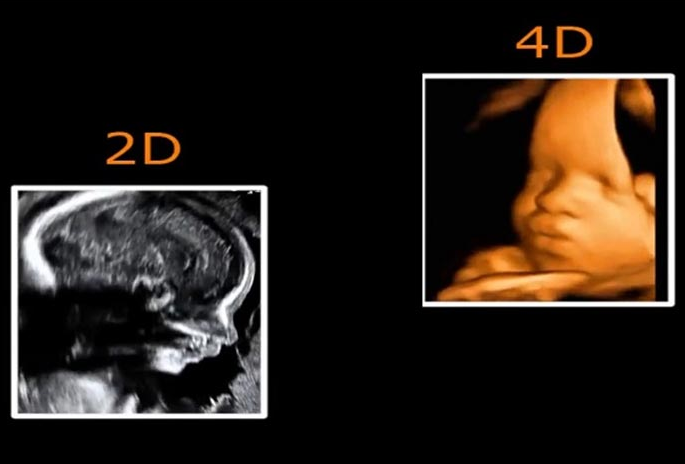

Siêu âm 4D là phương pháp siêu âm hiện đại, nâng cấp hơn so với phiên bản 2D, 3D trước đó. Nếu siêu âm 2D có hình ảnh mặt cắt theo không gian 2 chiều thì siêu âm 3D là hình ảnh thể hiện không gian 3 chiều với nhiều góc độ khác nhau. Siêu âm 4D là siêu âm gồm 3 chiều không gian và 1 chiều thời gian.

Như vậy, siêu âm 2D và 4D khác nhau thế nào? Sự khác nhau của siêu âm 2D và 4D là ở cách thể hiện hình ảnh và bác sĩ sản khoa sẽ ứng dụng loại siêu âm nào tùy vào từng giai đoạn cụ thể của thai kỳ.

Để giải đáp cho thắc mắc siêu âm 2D hay 4D cái nào chính xác hơn, mẹ bầu cần so sánh ưu và nhược điểm của từng loại siêu âm như sau:

Như vậy, không thể kết luận siêu âm 2D và 4D cái nào chính xác hơn vì hai kỹ thuật này đều chính xác và tùy thuộc vào thời điểm của thai kỳ, nhu cầu cũng như khả năng tài chính mà mẹ lựa chọn hình thức siêu âm nào phù hợp.